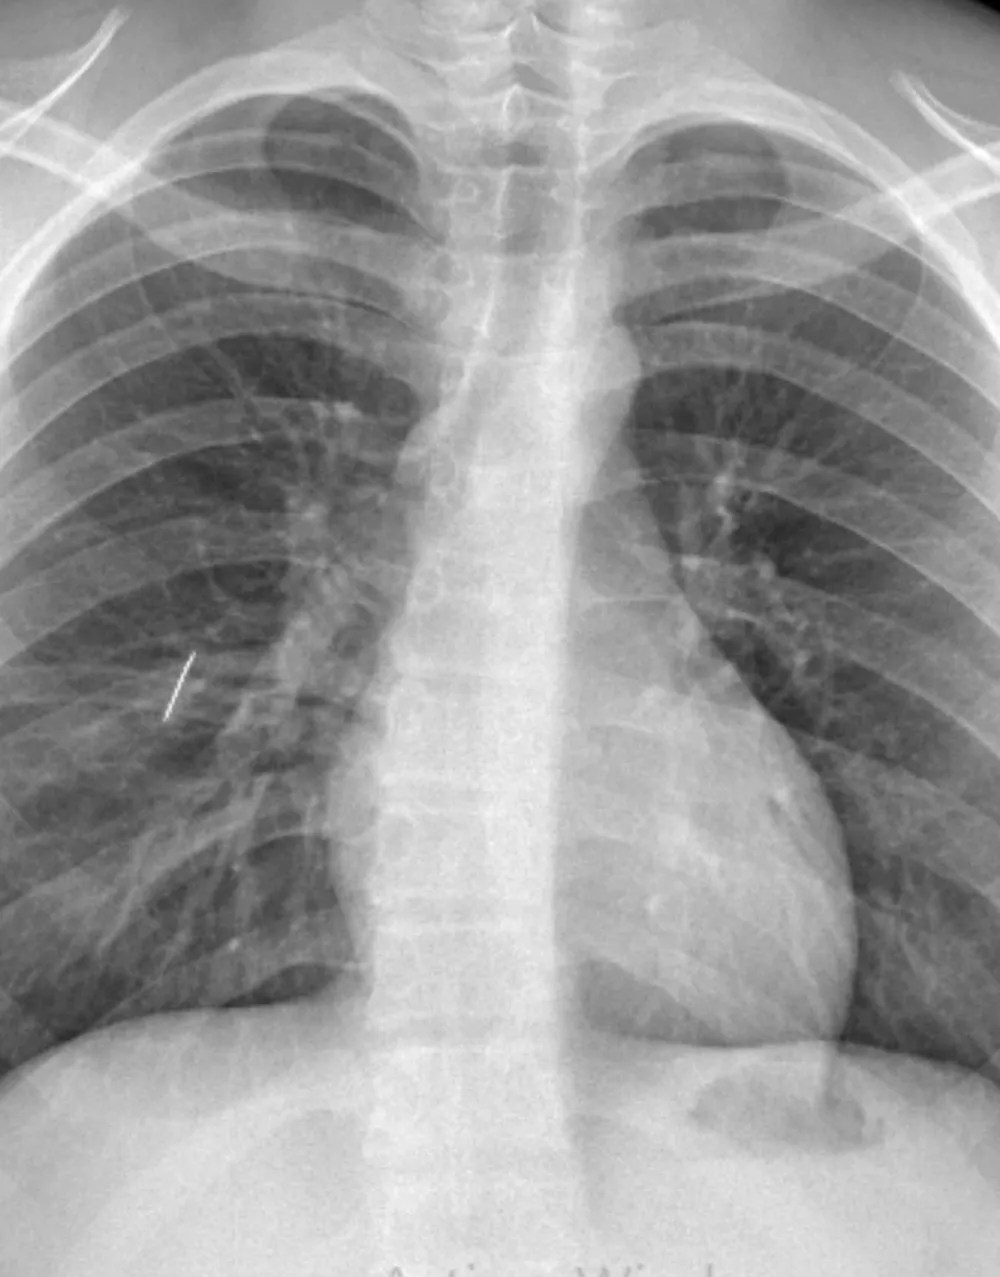

El paciente había ingresado por guardia tras sufrir un accidente doméstico que le provocó un trauma penetrante de tórax.

Tras recibir una primera atención en su localidad, el adolescente fue derivado al hospital capitalino, donde se confirmó la presencia del objeto metálico en el pulmón. El equipo de Emergencias realizó un drenaje torácico inicial, pero al no lograr la expansión pulmonar debido al cuerpo extraño, se decidió avanzar con una intervención quirúrgica de alta complejidad.

Los profesionales destacaron que este tipo de casos no admite derivación, ya que el traslado por vía terrestre o aérea hubiese implicado un altísimo riesgo de vida. “Era un trauma penetrante de tórax con una aguja de coser incrustada en el pulmón. La resolución debía hacerse aquí y con satisfacción podemos decir que fue realizada por nuestro equipo”, explicó el Dr. Lestussi.